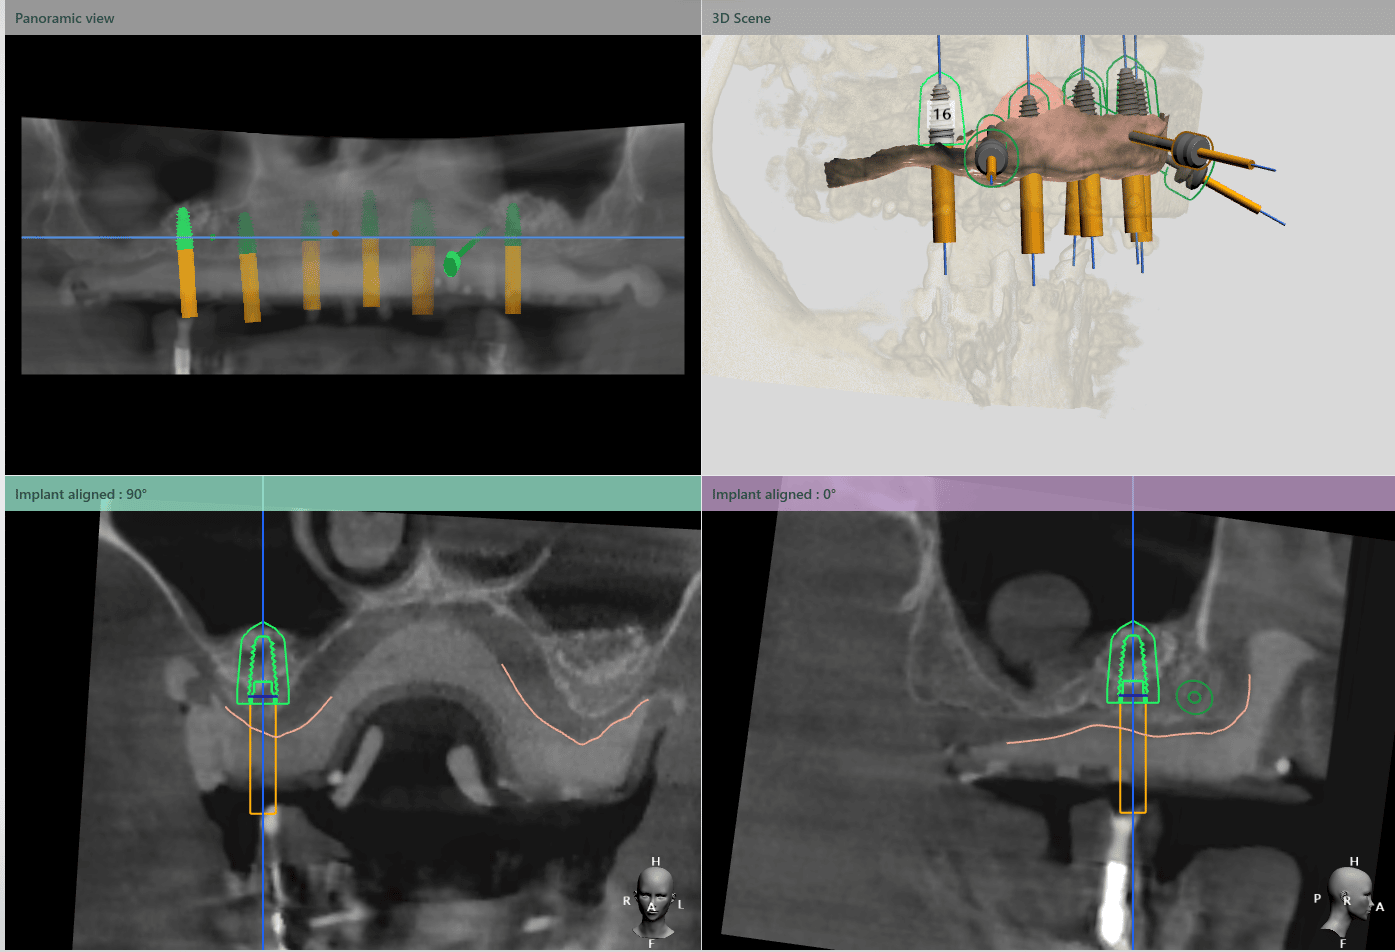

Medicul specialist a efactuat scanarea digitală a arcadelor pe care a trimis-o tehnicianului dentar DigiRay, împreună cu CBCT-ul pacientului.

Odată planficată și agreată poziția și axul de inserție al fiecarui implant, tehnicianul DigiRay efectuează designul șablonului chirurgical și printarea acestuia dintr-o rășină bio-compatibilă.

Ulterior, tehnicianul editează protocolul și secvența de frezare conform sistemului de implanturi și trusei chirurgicale folosite de către medic și îl trimite prin email medicului curant.